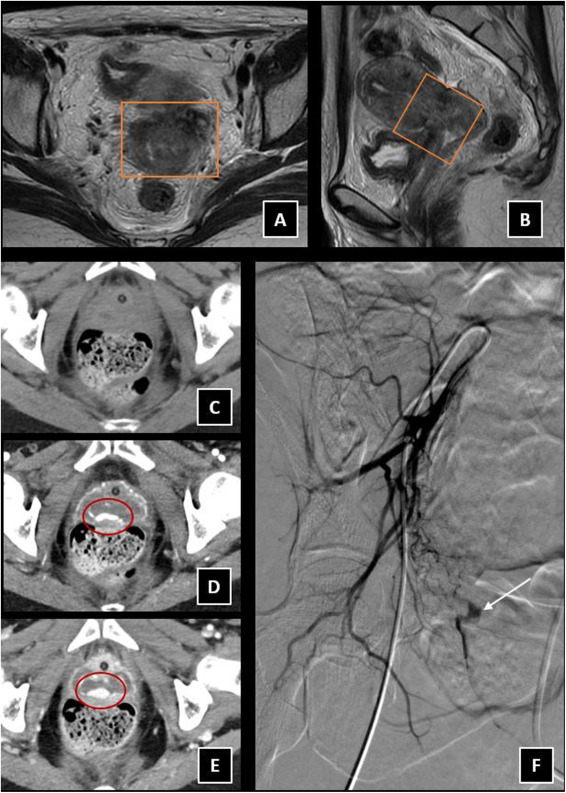

Os comparto nuestra última revisión sobre el papel de la radiología intervencionista en el sangrado uterino anormal. @D_Vas_ @MaarioMatute @fermgmez @SERVEISoc @SERAM_RX @residentesSERAM Enlace para descargarlo gratuito durante 50 días authors.elsevier.com/a/1fzFc,4oRACg…